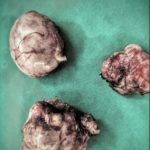

Γυναίκα ηλικίας 69 ετών, υποβλήθηκε σε λαπαροσκοπική ολική υστερεκτομή λόγω εξαρτηματικου όγκου. Η ασθενής εξήλθε από την κλινική, την επόμενη μέρα.

Η διάγνωση κατά τον υπερηχογραφικό έλεγχο που έδειξε ότι δεν πρόκειται για απλή κύστη αλλά για εχινόκκοκο κύστη στη δεξιά ωοθήκη, ισχυροποιήθηκε κατά τη διενέργεια μαγνητικής τομογραφίας και επιβεβαιώθηκε μετά την επέμβαση, με την ιστολογική εξέταση.

Η εχινόκκοκος κύστη είναι μια πλέον όχι τόσο συχνή πάθηση σε σχέση με την προηγούμενη δεκαετία στην Ελλάδα. Με εντόπιση στην ωοθήκη υπάρχουν ελάχιστες βιβλιογραφικές αναφορές. Ο Γυναικολόγος πρέπει να διαθέτει εμπειρία και να μη ξεχνά ότι παρ΄ ότι σπάνια δεν πρέπει να αποκλείεται.